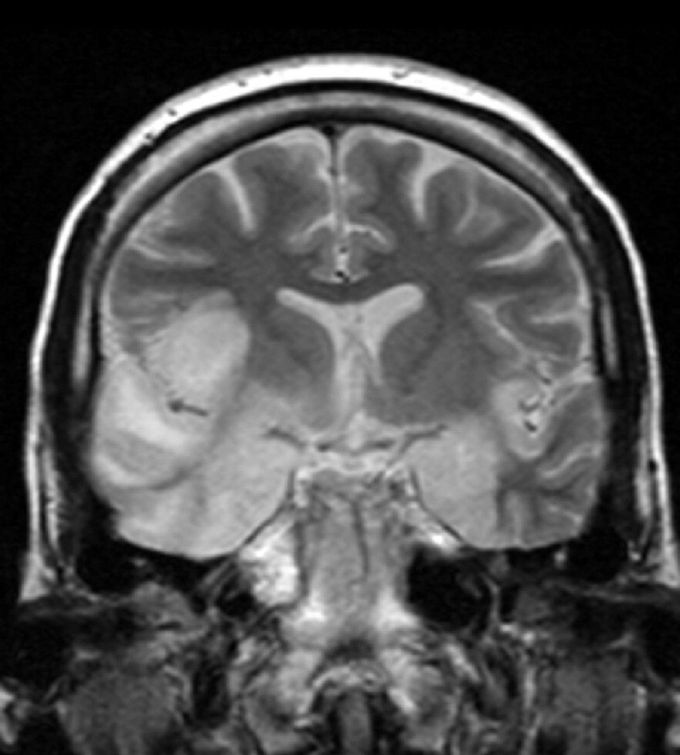

Encephalitis

Encephalitis (Greek ἐνκεφαλίτις, brain inflammation) - inflammation of the brain (the suffix "it" indicates the inflammatory nature of the disease). The term "encephalopathy" indicates the absence of inflammation, and the process of lesion is mainly caused by vascular disorders. It is often a clinical syndrome of many diseases.